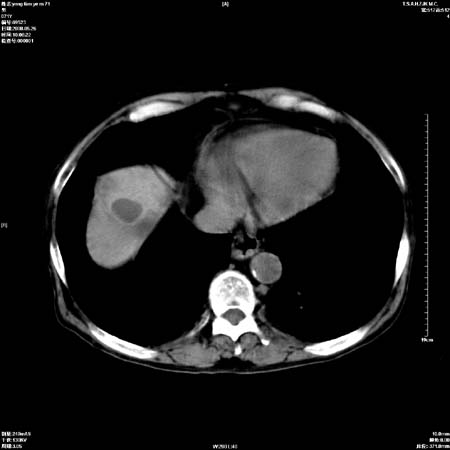

以下是引用医影拾贝在2008-6-5 22:48:00的发言:[br]肝硬化、门脉高压、胃底食管静脉曲张、低蛋白血症(胆囊壁水肿、增厚)、腹水[br]脾功能亢进、脾大、脾、左肾囊肿[br]肝囊性占位、不除外肝脓肿可能[br]建议增强以除外肝右叶肝ca可能

以下是引用chenglinhunan在2008-6-5 22:53:00的发言:[br]1. 肝硬化腹水,脾肿大。[br]2. 肝右后叶占位,肝癌。[br]3。建议ct增强扫描。

以下是引用xulianj在2008-6-5 21:40:00的发言:[br]支持肝硬化腹水;建议增强。肝、脾、肾囊肿待排。

以下是引用zjzjr在2008-6-6 12:34:00的发言:[br]1. 肝硬化腹水,脾肿大。[br]2. 肝右后叶占位,肝癌。[br]3。建议ct增强扫描。[br]4肝脾囊肿.